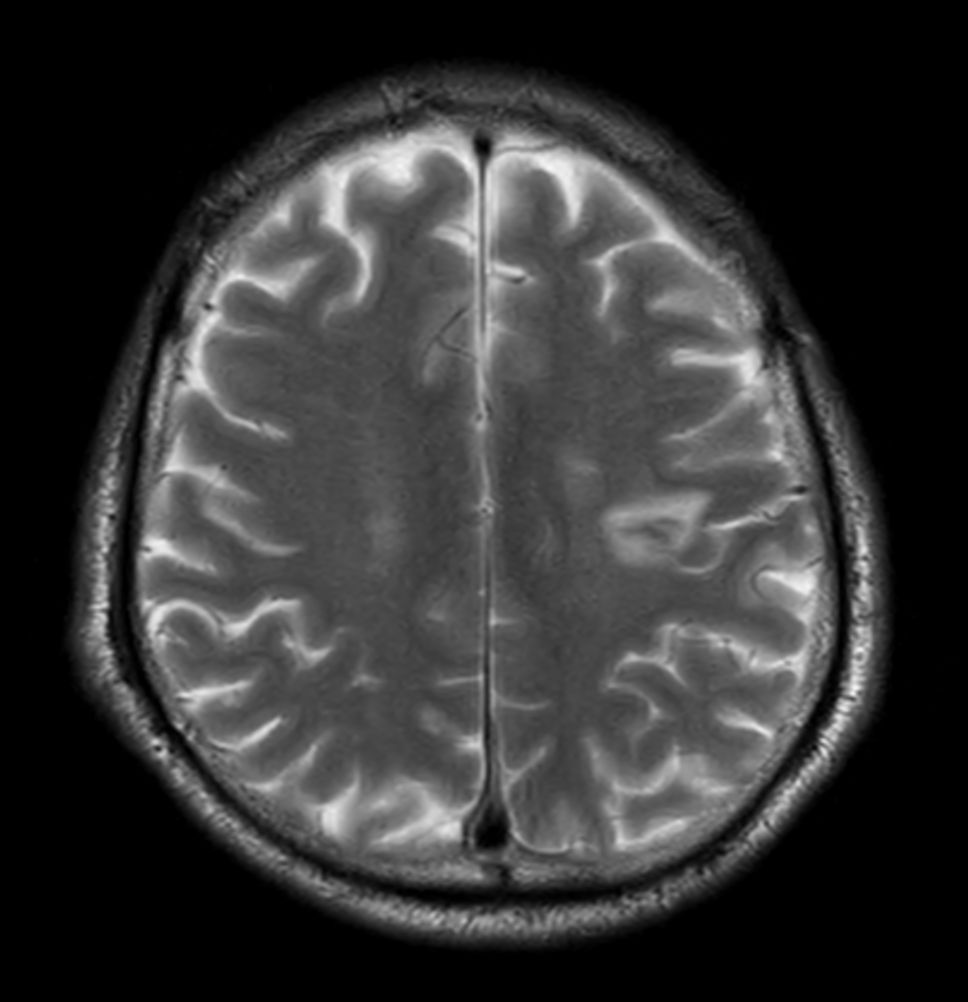

Patient with a small brain infarction. Compressed SENSE acceleration is used to speed up sequences while maintaining equal image quality. Three different diffusion methods are included; A fast 52 secs DWI EPI sequence, a high resolution DWI EPI sequence and a TSE based DWI sequence. A SWIp sequence is included offering high resolution 3D susceptibility weighted imaging to enhance contrast for deoxygenated (venous) blood or calcium deposits. 3D APT sequence is included providing contrast-free brain imaging, addressing the need for more confident diagnosis in brain neuro oncology by using the presence of endogenous cellular proteins to produce an MR signal. And a large FOV TOF MR Angiography sequence is included to check on brain vascular anatomy.

Axial T2w TSE - Compressed SENSE